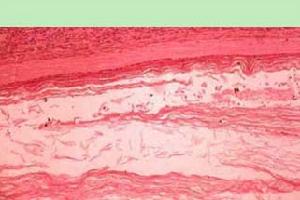

在顯微鏡下,可見瘤壁由兩層組織構成,外層為一薄層的纖維結締組織,內層為復層鱗狀上皮,上皮層面向囊腔,表面有很多角化細胞,不斷脫落形成囊內容物並使腫瘤不斷增大,與腫瘤相鄰的蛛網膜組織呈纖維增生及玻璃樣變,有時還可見異位巨噬細胞、淋巴細胞及組織細胞的浸潤。囊的內容物具有組織毒性,溢出到蛛網膜下腔可以引起肉芽樣炎症反應。與囊緊鄰的腦組織可有膠質增生。